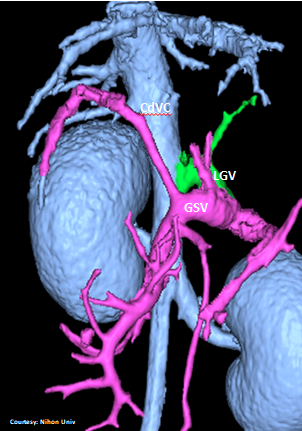

Does LEFT GASTRIC VEIN (LGV) enter the GASTROSPLENIC VEIN (GSV)?

“LGC +PancV -GSV” Left Gastro-Caval Shunt with Pancreatic Vein contribution and absent Gastro-splenic vein (GSV does not enter PV)

Courtesy: Nihon Univ